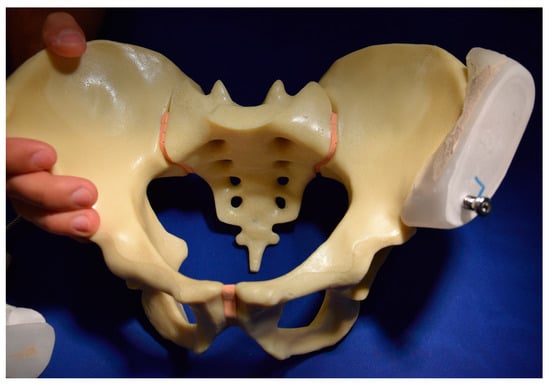

2. Materials and Methods

2.1. Biomechanical Testing